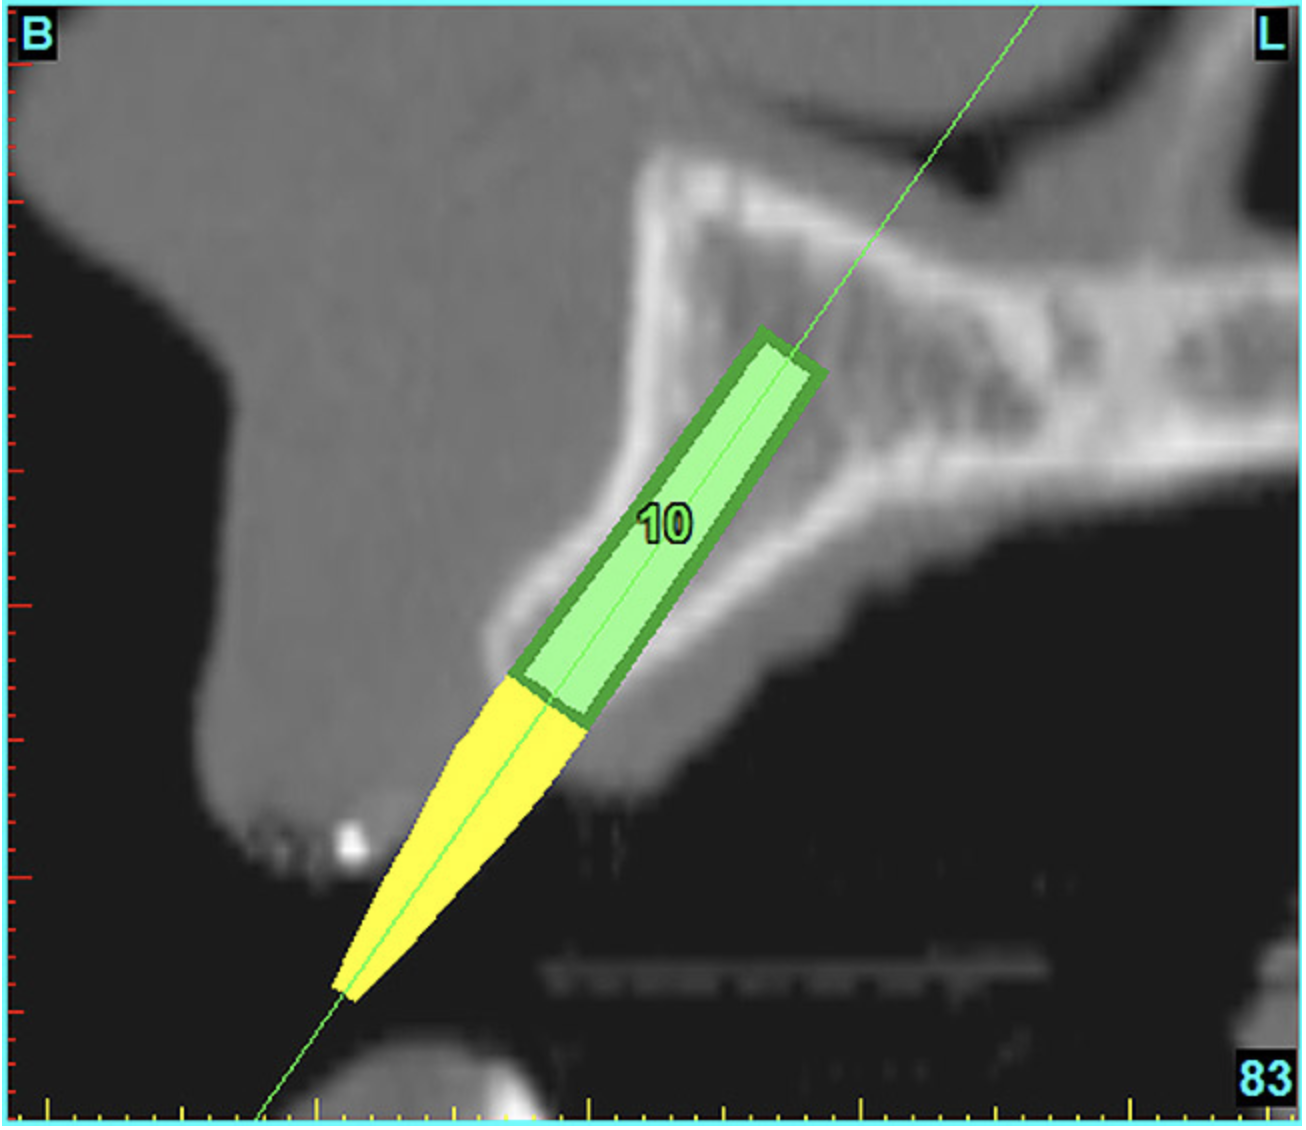

After the basic plan had been established, it was re-evaluated using interactive 3D images. The reconstructed 3D view of the maxilla clearly illustrated the extent of the bilateral facial concavities, and the root eminences of the adjacent and posterior teeth (Figure 7A). The placement of the virtual implants then was evaluated to ensure that the facial cortical plate was not perforated (Figure 7B). The implants were labeled individually as “7” and “10,” with the simulated yellow abutment projection indicating the facial-lingual inclination through the bone to the level above the incisal edge of adjacent teeth. The ability to gain a better understanding of these individual root forms can not be underestimated. The dental literature has suggested certain parameters for placing implants near teeth and implants next to other implants. However, there is little scientific 3D documentation to support these suggested rules.5-10 The use of an interactive treatment-planning software application permits closer scrutiny of previously difficult-to-visualize areas, and can now be used to redefine perceptions of spatial positioning of implants, especially when in close proximity to natural tooth roots, vital anatomy, and adjacent implants.27-29

Figure 7a  The 3D reconstruction showed (A) the facial concavities and root eminences, and allowed (B) for evaluation of virtual implant placement to ensure the facial cortical plate was not perforated.

Figure 7a

Figure 7b  The 3D reconstruction showed (A) the facial concavities and root eminences, and allowed (B) for evaluation of virtual implant placement to ensure the facial cortical plate was not perforated.

Figure 7b